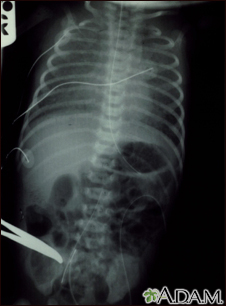

Totally anomalous pulmonary venous return - X-ray